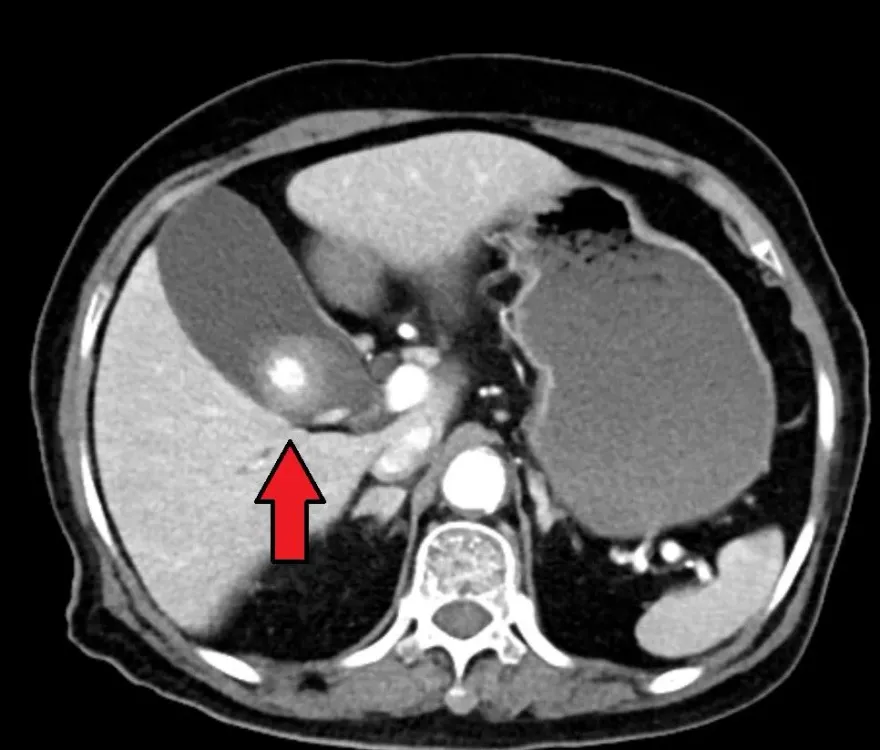

膽結石

膽囊炎

結石